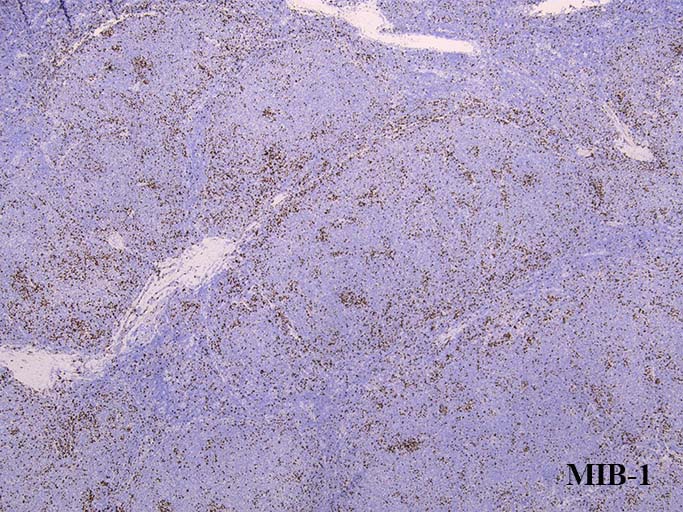

prototypeと同様濾胞内細胞のMIB-1 LIは低値をしめしているようである. (陽性はT-cell)

増殖細胞はMIB-1陰性が多い. びまん性に増殖リンパ球がCD23陽性を示す. CD21は陰性(上, loupe像)

BCL6は陽性コントロールと比較しても同程度に陽性を示している。初発のdiffuse lymphoma cellのように弱陽性ではない. MIB-1陽性細胞が集簇して認められる. labeling indexは濾胞全体では低値である.